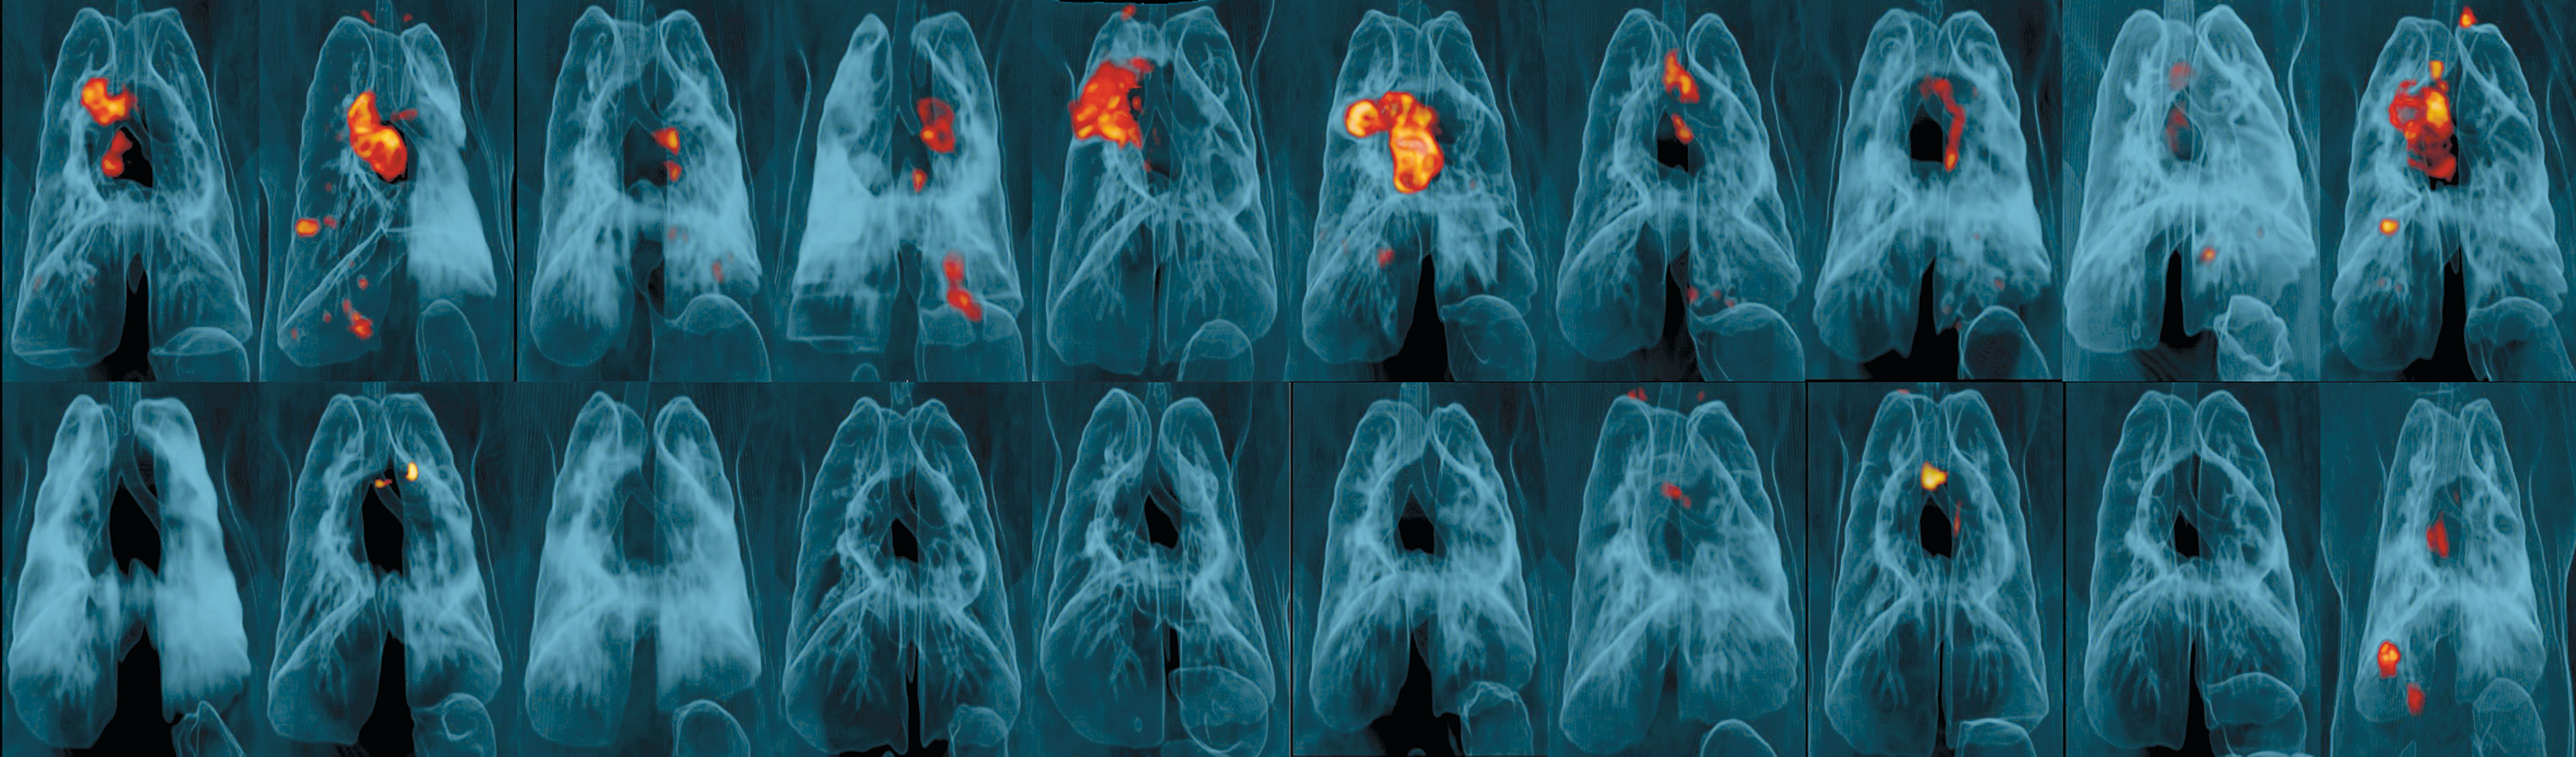

Lungene til apene i studien. Det røde og gule viser betennelse fra tuberkulose. Dyrene på øvre rad fikk BCG-vaksinen…

Lungene til apene i studien. Det røde og gule viser betennelse fra tuberkulose. Dyrene på øvre rad fikk BCG-vaksinen intradermalt og apene på den nedre rad fikk vaksinen intravenøst. Illustrasjonsfoto: AP/NTB Scanpix

Nyere immunologisk innsikt tilsier at vaksine direkte til lungene eller øvre luftveier er bedre egnet enn intradermal vaksine for å forhindre dråpesmitte av tuberkulose. Denne hypotesen ble prøvd ut i en ny studie, der fem grupper av makakaper ble gitt en høy dose BCG-vaksine (i) direkte til lungene med aerosol, (ii) intravenøst, (iii) intradermalt, (iv) aerosol pluss intradermalt, eller (v) intradermalt i vanlig lav dose (1). Etter seks måneder ble apene smittet med høyvirulent M. tuberculosis. Undersøkelse av vaksineringsresponsen ble gjort bl.a. ved å karakterisere mononukleære, antigenspesifikke leukocytter i blod og bronkioalveolærvask, genaktivering i leukocyttene, 18F-fluorodeoksyglukose-PET-CT-avbilding av granulomer i lungene og histologi på og bakteriedyrkning fra autopsimateriale.

Bare intravenøs vaksinering, som ga nesten fullstendig immunitet, var effektiv. Ni av totalt ti aper fikk en høy grad av beskyttelse, og hos seks av disse ble det ikke funnet noen spor av tuberkulosebakterier. Sammenlignet med de andre vaksinasjonsmåtene ga intravenøs vaksinering en massiv tilstedeværelse av langlivede T-lymfocytter, CD4- og CD8-celler, i lungene – vev, lymfeknuter og bronkioalveolær lavage. Immunresponsen ble antatt å være T-hukommelsesceller i lungevevet.